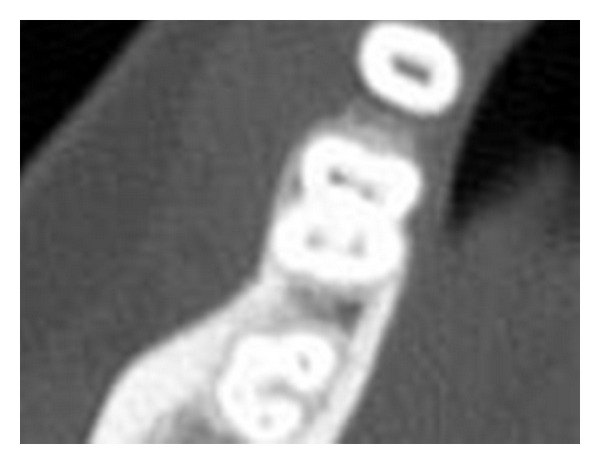

Case 1. A 22-year-old Indian female patient reported complaining of pain in a lower-right posterior tooth for a few days. The lower right first molar tooth had been restored with an amalgam restoration 10 years prior to this. Examination of the tooth revealed a large occlusal amalgam restoration with marginal ditching and tenderness to percussion. The mobility of the tooth was within physiologic limits and vitality testing revealed the tooth to be nonvital. The medical history of the patient was noncontributory. Radiographic examination (Figure 1(a)) revealed the restoration close to the distal pulp horn and periapical lamina dura widening. It also revealed the presence of an additional supernumerary root on distolingual side. In addition, a computed tomographic scan (Figures 1(b), 1(c), and 1(d)) of the lower jaw of the patient was available for surgical reasons. On evaluation, the scan illustrated the nature of origin and curvature of the extra root in a mesiobuccal direction as depicted by the arc (Figure 1(d)). The extra root originated from the distolingual part of the tooth and curved mesially.

The infrequent occurrence of such an anomaly requires that the clinician be vigilant in diagnosis and management of the lower molar teeth. The clinical examination of the tooth can reveal a more bulbous outline of the crown, an extra cusp (tuberculum paramolare), or a more prominent occlusodistal or distolingual lobe. These in combination with a cervical prominence or convexity can indicate the presence of an additional root. Aids to clinical examination such as magnifying loupes, an intraoral camera, or a dental microscope may be useful in this respect. Radiographically a third root should normally be readily evident in about 90% of cases [20]. A careful inspection of the radiograph can sometimes reveal the presence of a “hidden” RE as indicated by an unclear view or outline of the distal root contour or the root canal. However, it may still be missed due to its slender dimensions occasionally. An additional exposure of the concerned tooth from different horizontal projections, the standard buccal-to-lingual projection, 20 degrees from the mesial and 20 degrees from the distal reveals all the basic information regarding the anatomy of the tooth [21, 22]. Cone-beam computed tomography has emerged as a useful tool to aid in diagnosis of complex root canal anatomy. In the first case report the CBCT images revealed the location and direction of the curvature. This was extremely beneficial during cleaning, shaping, and obturation of the type 3 curvature seen in this root.